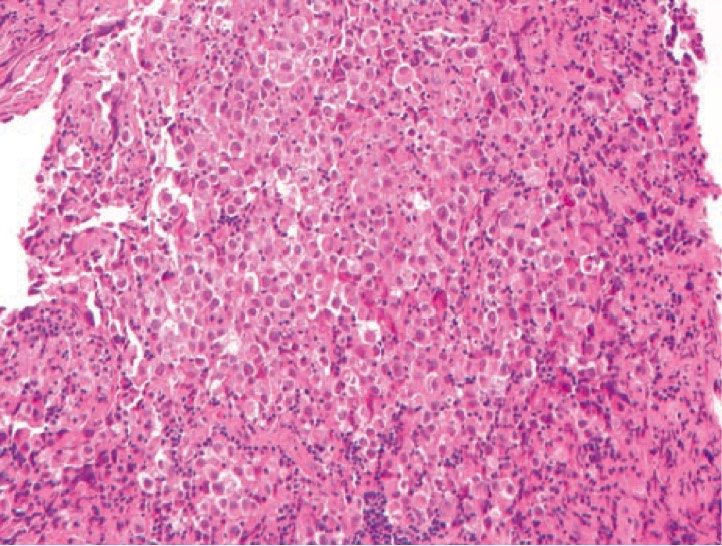

представлен биоптат гипофиза 14-летнего мальчика, диагноз

1061. На микрофотографии представлен биоптат гипофиза 14-летнего мальчика, диагноз